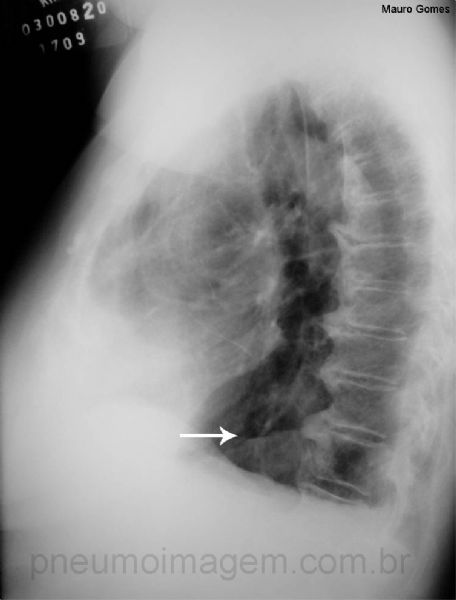

Pela radiografia em perfil, a hérnia de hiato pode ser observada posteriormente ao coração (seta branca). Observe o nível hidraéreo do conteúdo gástrico, que pode ser confundido com abscesso pulmonar.

Chaves: nível líquido; bolha gástrica; estômago; gastric air bubble; stomach.